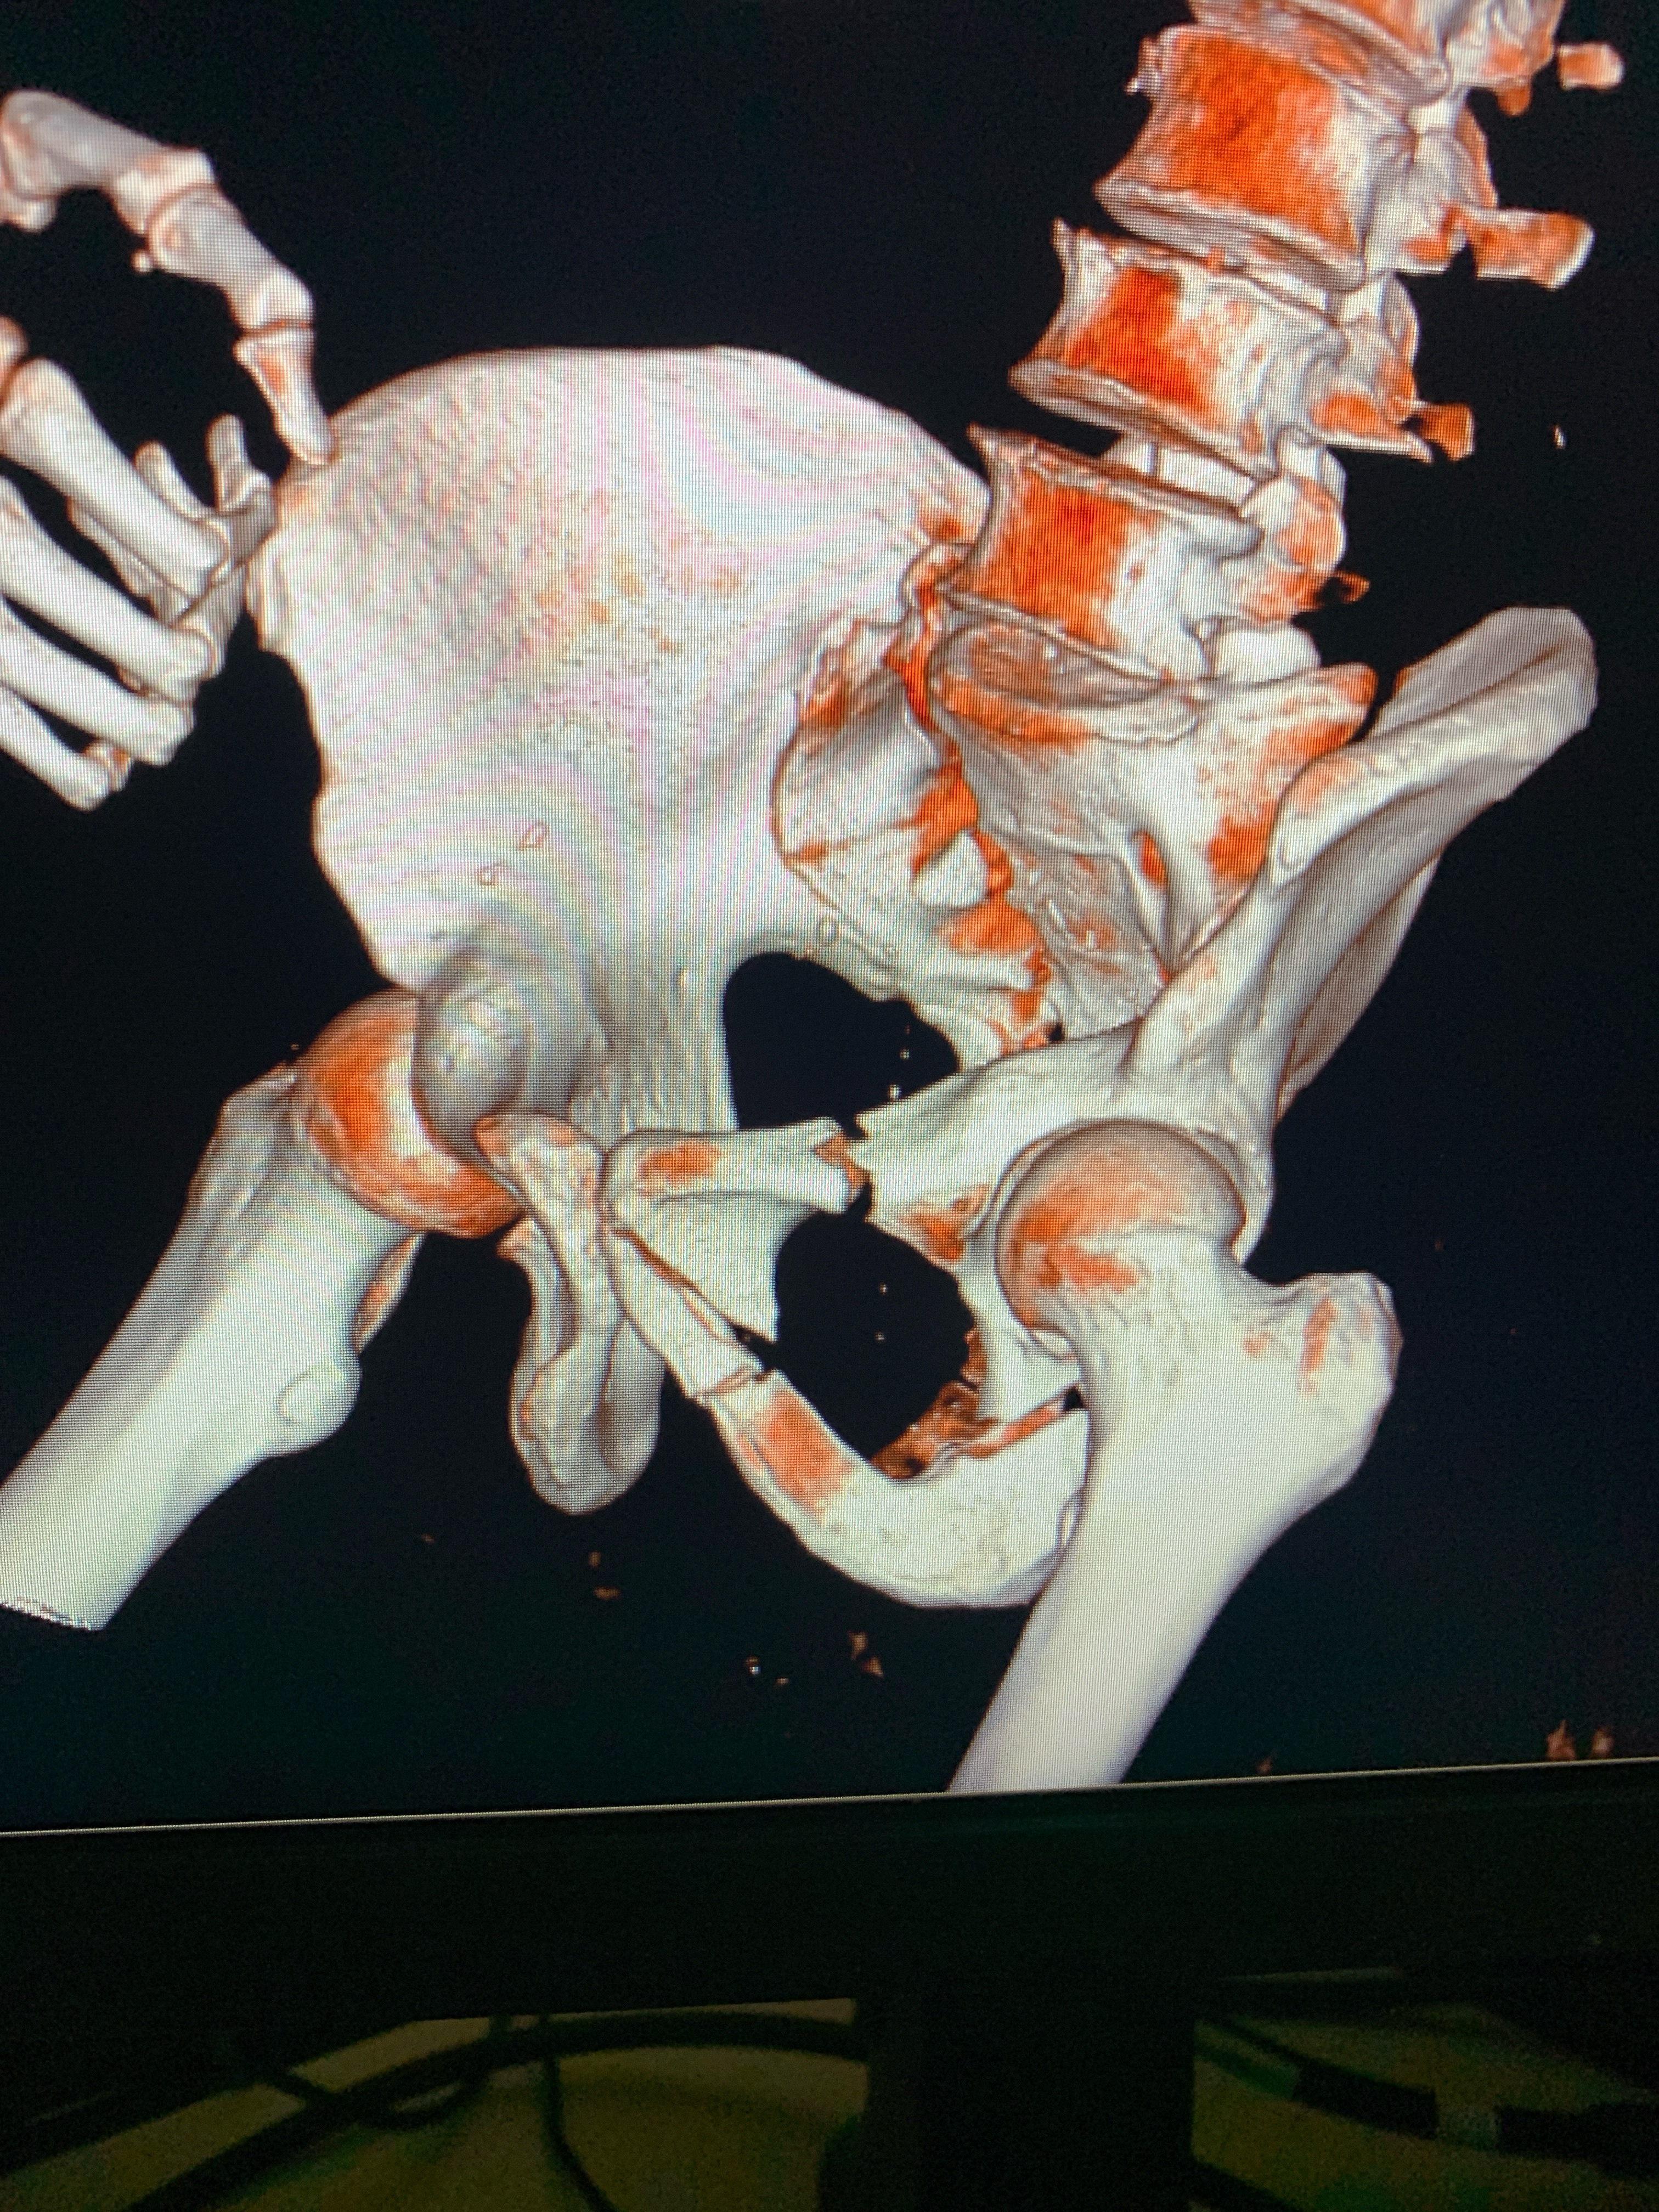

IMG20251208122511.jpg

Здравствуй двачик, сегодня мы с вами опять будем играть в рентгенолога, я вам буду постировать фоточки, а вы узнавать пиздецомы на них.

А пока мы обсуждаем этот сложный вопрос я вам фоочки буду показывать! Штош погнали!